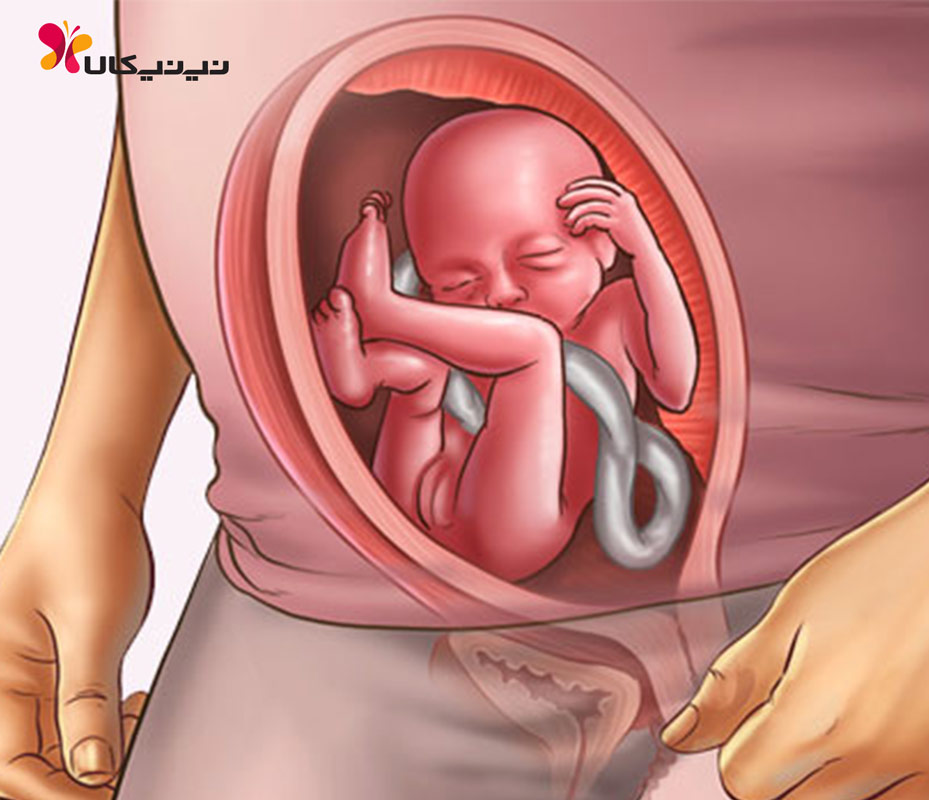

Расположение плода на 15-й неделе беременности: фотографии и иллюстрации